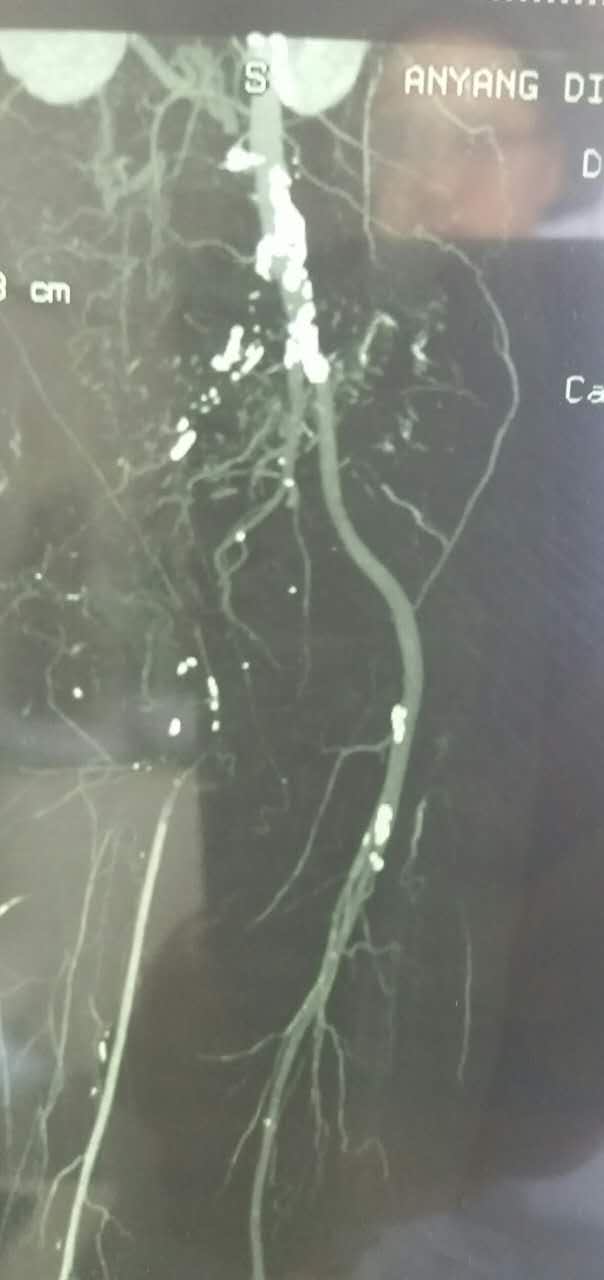

入院后,结合病史,考虑有血栓形成的可能性,行全身静脉溶栓,一周后复查CT,右侧髂总动脉出现一段管腔

对比正常解剖模式图,我们可以发现:右侧髂总髂内髂外股总动脉未显影,股深动脉未显影,右侧股浅动脉起始段未见显影,考虑有血栓闭塞的可能。